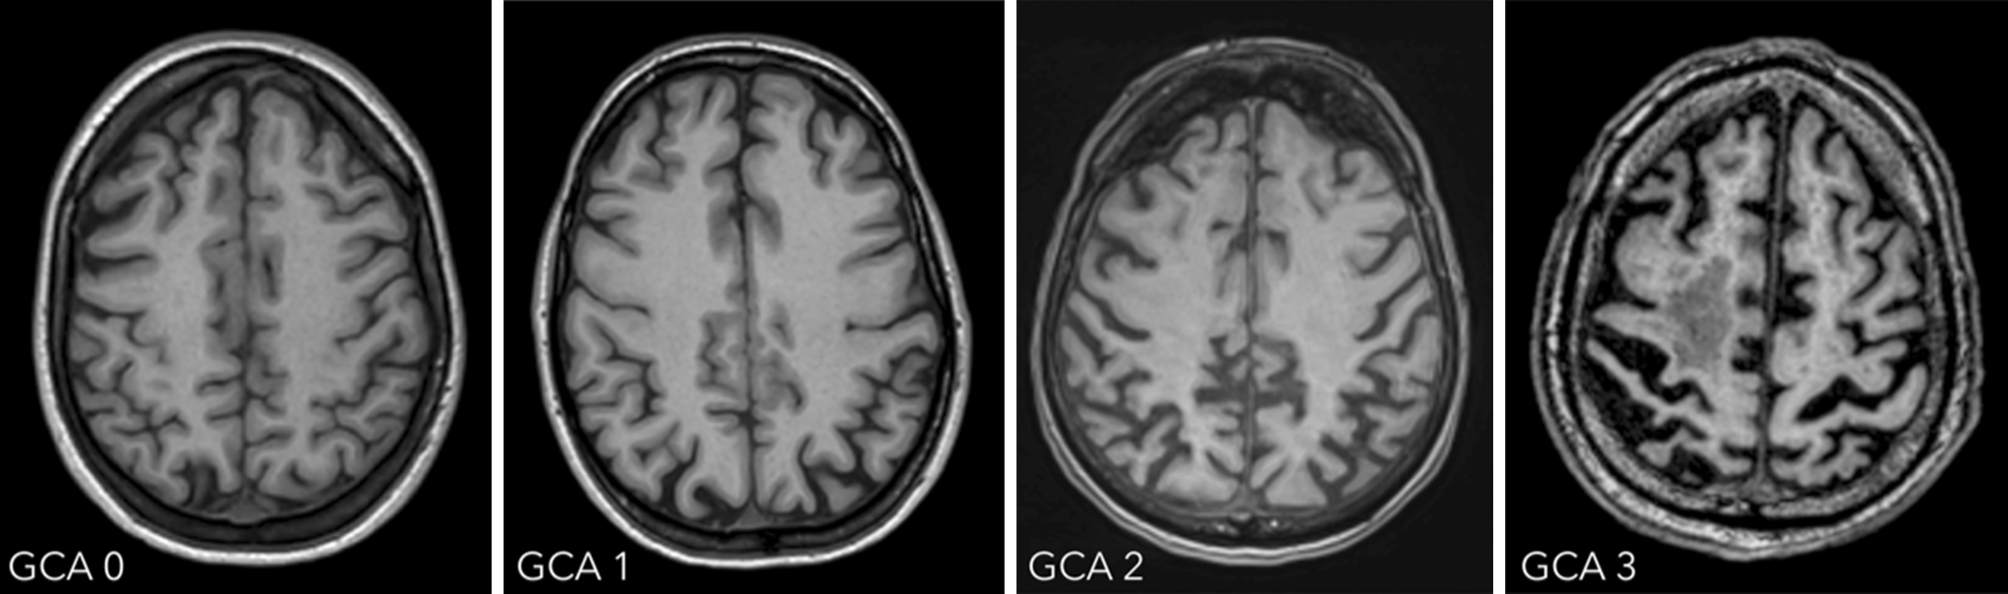

Global cortical atrophy

The four-step global cortical atrophy (GCA) scale proposed by Pasquier ranges from 0 = no atrophy to 3 = knife-blade atrophy (illustrated in Fig. 1; [1]). GCA 0 represents a normal volume of the gyri and a normal width of the sulci; GCA 1 indicates mild atrophy with a still-normal volume of the gyri but some open sulci; GCA 2 describes moderate brain atrophy with a reduction of gyri volume and a moderate enlargement of the sulci; and GCA 3 illustrates severe atrophy with severely reduced gyri and enlarged sulci. In addition, the focal regions of brain atrophy should be given.

Fig. 1

Global cortical atrophy scale